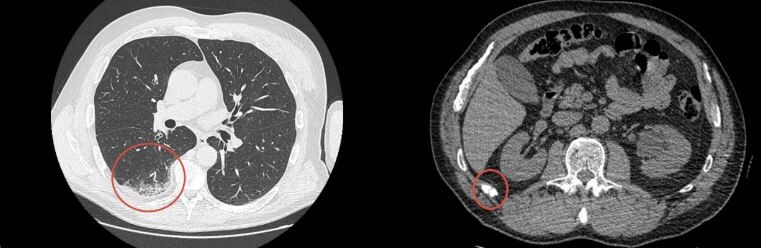

Дистальная резекция поджелудочной железы с сохранением селезенки: клинический случай

Основной задачей, помимо радикального удаления опухоли, было сохранение селезенки. Несмотря на значительные размеры образования, хирургам удалось сохранить орган, что имеет принципиальное значение для поддержания иммунного статуса и качества жизни молодой пациентки в будущем. В ходе вмешательства было проведено срочное гистологическое исследование. Морфологический анализ в режиме реального времени подтвердил наличие нейроэндокринной опухоли (НЭО), что позволило врачам окончательно верифицировать диагноз и подтвердить адекватность выбранного объема резекции непосредственно в операционной. На сегодняшний день пациентка переведена из отделения интенсивной терапии в палату стационара. Состояние стабильное, начат протокол ранней послеоперационной реабилитации. Главный итог — тот факт, что спустя сутки после такой серьезной операции человек уже восстанавливается в палате, — лучшая оценка работы всей команды: анестезиологов, реаниматологов, хирургов и медицинских сестер. При дистальной резекц